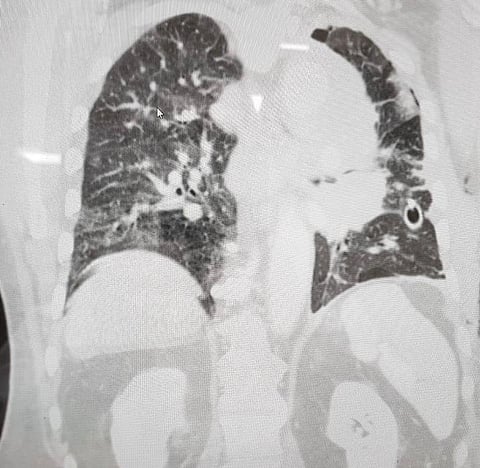

المريض كان يعاني تجمعًا مائيًا مزمنًا على الرئة اليسرى نتج عنه آلام شديدة بالصدر والذي تسبب أيضًا بانكماش تام بالرئة مع ترحيل للفراغ المنصف ووجود ورم على الشريان الأبهر والرئوي الأيسر مع تكتلات في الغدد الليمفاوية استدعى التدخل الطبي لتحرير الغشاء البلوري وأخذ عينات عن طريق الشق الصدري.

وقد قرر الفريق الطبي المعالج أنه نظرًا لعمر المريض 75 عامًا أن الشق الصدري يحمل خطورة عليه وقد تقرر إجراء عمل منظار لجراحة الصدر وبفضل الله تمكن الأطباء من إجراء المنظار بالتعاون مع قسم التخدير بإجراء التخدير عن طريق أنبوبة حنجرية مزدوجة المسار بفصل الرئة اليسرى بالكامل أثناء الجراحة وقد تمت العملية بنجاح.